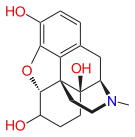

- Hydroxycodeine

Hydroxycodeine Hydroxycodeine |